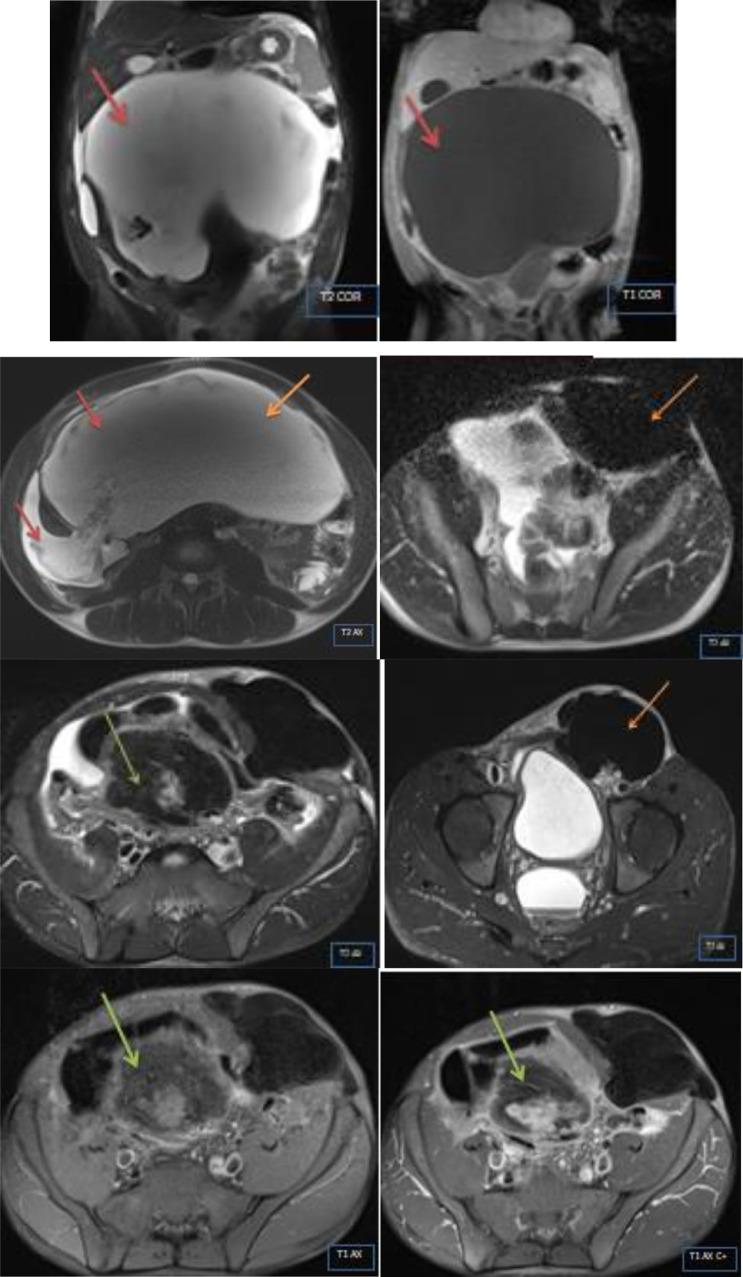

Desmoid tumors, also known as deep fibromatosis or desmoid-type fibromatosis, represent a rare subset of deep fibromatoses. It is a locally aggressive tumor, with no specific symptoms, and no metastatic potential. We report a case of a 38-year-old male patient with an abdominal mass. Radiological findings showed 2 tumors, the first was a solid inguinal mass of the left lateral iliac pedicle, and the second was a giant cystic mass in the abdominal cavity. An elective explorative laparotomy was performed to remove the 2 masses. Histopathological examination confirmed the desmoid tumor diagnosis of both lesions.

硬纤维瘤,也称为深部纤维瘤病或硬纤维瘤型纤维瘤病,是深部纤维瘤病中罕见的一种类型。它是一种局部侵袭性肿瘤,无特异性症状,也无转移潜能。我们报告一例38岁男性腹部肿块患者。影像学检查发现两个肿瘤,第一个是左侧髂蒂的实性腹股沟肿块,第二个是腹腔内的巨大囊性肿块。进行了择期剖腹探查术以切除这两个肿块。组织病理学检查证实两个病变均为硬纤维瘤。